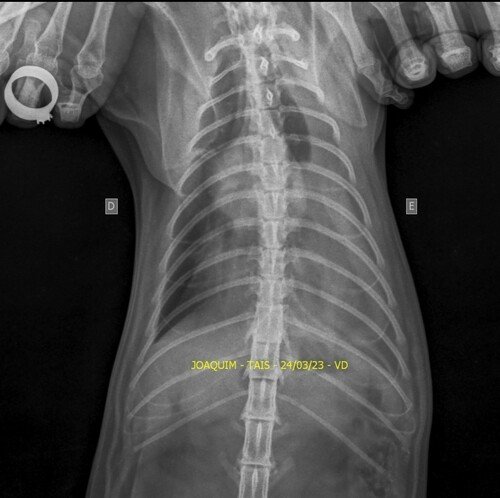

Venha aqui pedi ajudar de vocês. Meu gato, o Joaquim,sofreu um acidente no dia 14/03. Ele rompeu o diafragma e precisa de uma cirurgia urgente. Está com problema respiratório, teve umas lesões interna, uma lesão na pata traseira e não come devido o rompimento. Ele precisa fazer essa cirurgia o mais rápido possível.